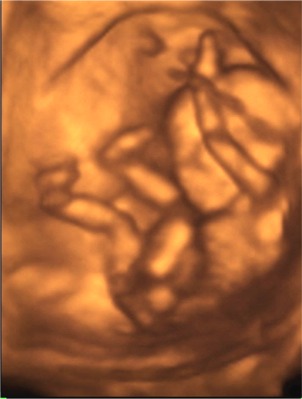

Megjöttünk a 4D-ről :) :) :)

Nagyon nagyon jó volt! Csúcsszuper :D

A babucim iszonyú jól érzi magát odabent, fészkelődik, rugdalózik megállás nélkül, ugyanúgy mint a 12 hetesen :lol:

Fejétől a lábujjáig 13cm .. persze ennél kisebb helyet foglal, mert fel van húzva a lába ..stb.

10,2 dkg a Lelkem :)

Láttuk a kis szívét, a 4 szívkamrát, az agyát... az agyféltekéket, a gyomrát, a húgyhólyagját .. szóval messze felülmúlta a vizsgálat minden várakozásunkat.

A csöppség nemét nem merték biztosra mondani, így ezzel kapcsolatban még izgulhatunk kicsit :lol: :lol:

A 2D alapján kislányt mondanának .. de a 4D-n néha láttunk gyanus elemeket. De az lehetett a szeméremajkak is .. mert ebben az időszakban még azok is csúcsosak :) nah majd kiderül időben :) A nő szerint ebben az időszakban még nem lehet 100%-osra mondani, ő nem szeret jósolgatni.

A pici hasamnak viszont megvan az oka .. a hátrahajló méhem egy dolog, de abban is leghátul, lent a medencémben fészkelte be magát a babuci, így egészen a szeméremcsontomhoz kellett bekukkantanunk .. és nagyon nehezen tudtuk őt követni. De szerencsére egyfolytában mozgott .. így mindenét meg tudtuk nézni, és elkaptunk nagyon jó pillanatokat!

A kiskönyvemben április 9re vagyok kiírva, ha a hosszú ciklust belekalkulálom, akkor április 13. Na az első UH-n április 19-et mondtak (ez 8 hetesen volt), aztán a 12 hetesen április 13-at, most pedig április 14-et :) :) Nagy különbségek nincsenek, így rendben fejlődik a Drága!!!!

Boldogság van!!!

Mindjárt megpróbálok fotót mutatni róla!

Kép \"mutatom az arcocskám\"

Kép \"vakarom a fejecském\"

Kép \"látjátok hogy tornázom?\"

Kép \"elfáradtam ... hátrabújok pihenni\"